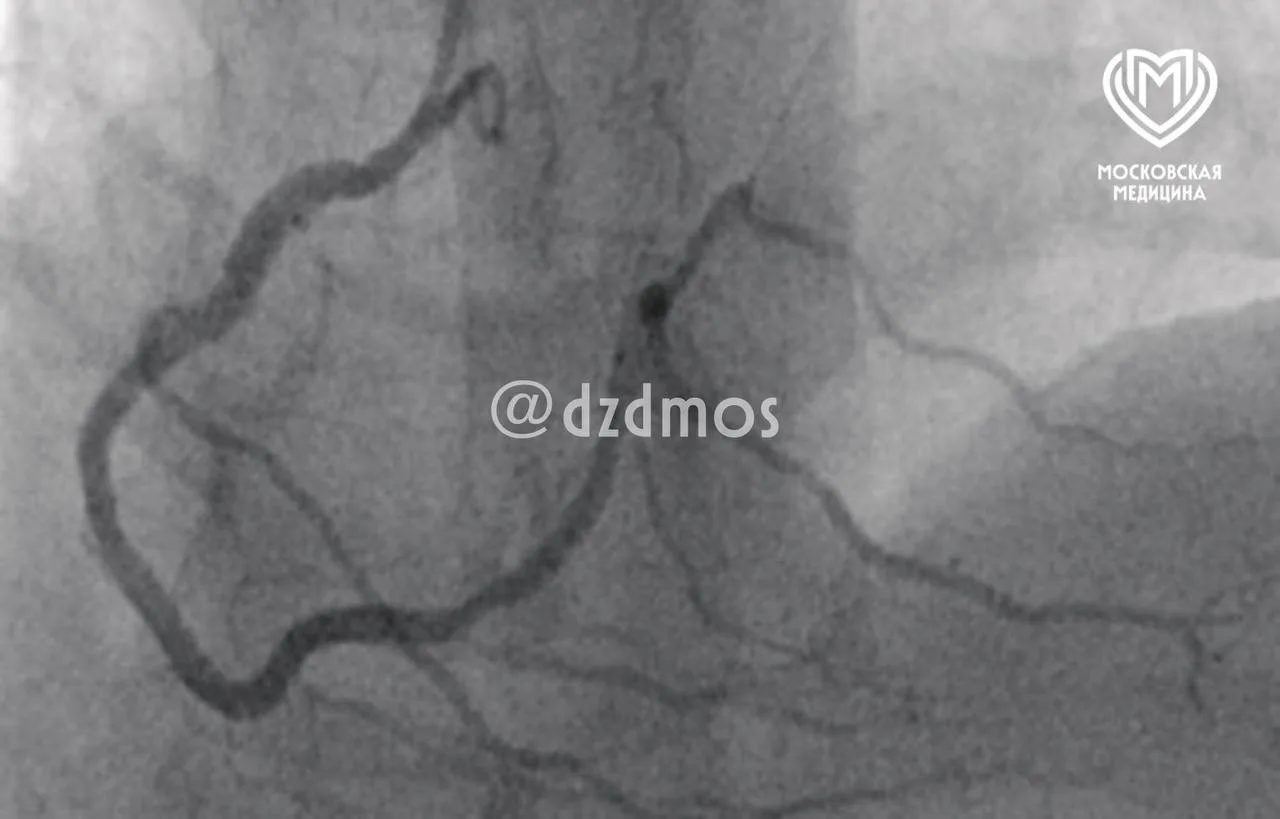

Московские хирурги удалили у пациентки 20-летнюю грыжу

О своём диагнозе женщина знала, но 15 лет болячка не беспокоила. Тяжело стало 5 лет назад, когда появились боли и грыжа сильно увеличилась в размерах.

Тогда женщина пришла за медицинской помощью. По словам хирурга Давида Цопурашвили, состояние женщины до операции угрожало её жизни.

Врачи московской больницы №52 прооперировали пациентку. После хирургического вмешательства ушла боль и улучшился внешний вид живота.

Пациентку выписали и дали ей все необходимые рекомендации для предотвращения рецидива.